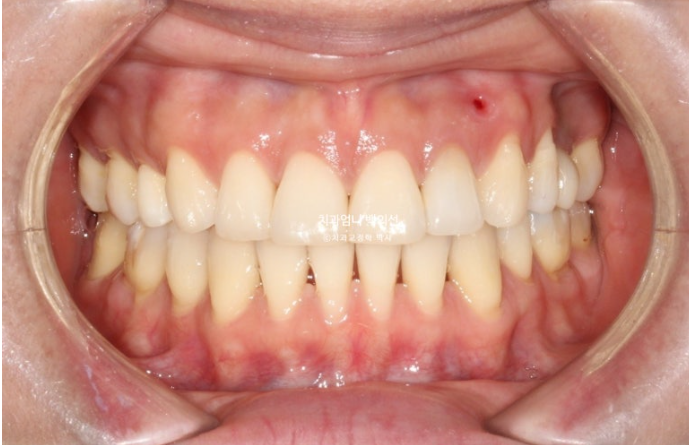

교합 안정화 및 마무리 과정을 거쳐 25년 6월, 드디어 재교정 치료를 마무리 했습니다.

25.06

총 치료기간은 1년 10개월 입니다.

이제 앞니 중심선은 코와 인중과 정확히 맞습니다.

2급이었던 양측 어금니 교합관계는 비로소 1급이 되었습니다.